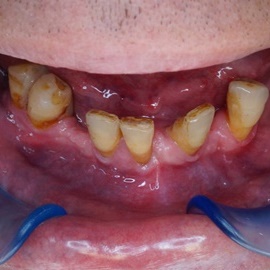

Skrócony łuk zębowy, kończący się na trójce. Blade atroficzne tkanki miękkie, relif dziąsła typu A, kość o małej gęstości, słabo ubeleczkowana i o kiepskim ukrwieniu. Niekorzystne warunki do odbudowy kości. Okres leczenia 1,5 roku, po odbudowie kości, zadowalający wynik końcowy w żuchwie, czas na korektę płaszczyzny zgryzowej.